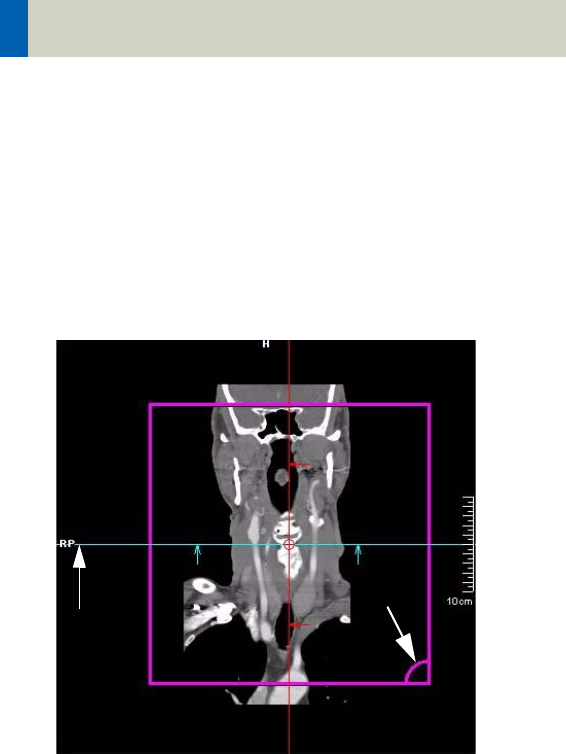

In each segment you will find a pink rectangle which

represents the boundary of the result images. The

image with the right down marker represents the field

of view (FoV) of the result images (viewing direction).

Right

down

marker

Reference lines

The rectangle with the grid represents the reference

image (topogram) which is added to the Topogram

series including the reference lines after reconstruc-

tion.

Topographics

indicator

Recon area